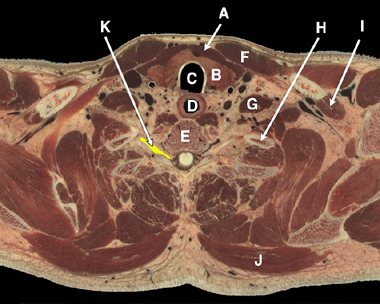

• Neck structures, low resolution